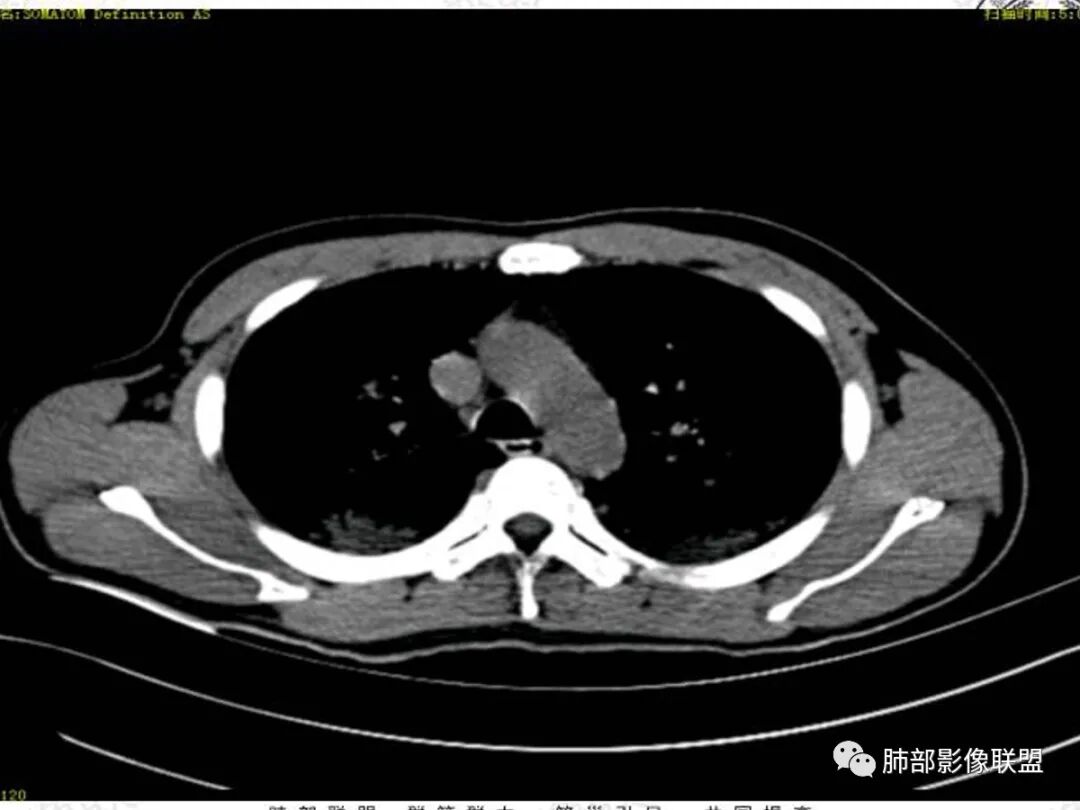

青年男性患者,气促7小时入院,白细胞及中性粒明显增高,PCT增高,CRP不高,心率快,呼吸急促,意识模糊,低氧血症,I型呼吸衰竭,PH偏低,失代偿性酸中毒,BNP偏高,胸部CT:双肺弥漫性多发斑片状实变密度影,双上肺明显,间质改变为主,综合:年轻男性,急性起病,迅速恶化,考虑中毒可能,鉴别:PCP,过敏,

37岁男性 气促 两肺对称分布磨玻璃及小叶间隔增厚,两肺上叶后段及下叶背段为著,有重力分布,下部密度较高,请结合病史排查肺水肿,理化性肺泡损伤

双肺叶透亮度对称性减低,呈磨砂状,小叶间隔规则增厚,上叶为甚,左右肺叶中轴间质增厚(示淋巴回流障碍),双肺叶弥散磨GGO征,以肺腺泡分布,双肺上,下叶融合片状,有重力分布特点,心脏大,肺动脉干增粗,首选心源性肺水肿,但无胸腔积液。与急性肺损伤和ARDS鉴别

青年男性,气促7小时入院,意识模糊,白细胞及中性粒明显增高,PCT增高,CRP不高,心率快,体温正常,血压正常。胸部CT:双肺上叶小叶间隔光滑增厚,中轴间质增厚,弥漫性磨玻璃、多发斑片影,以上肺、背侧分布为主。影像表现考虑为肺水肿。病因:病史不支持肾功能衰竭、心源性、高原性肺水肿,无发热,似乎也不支持细菌、病毒、真菌等感染引起。吸入毒物?吸入水?